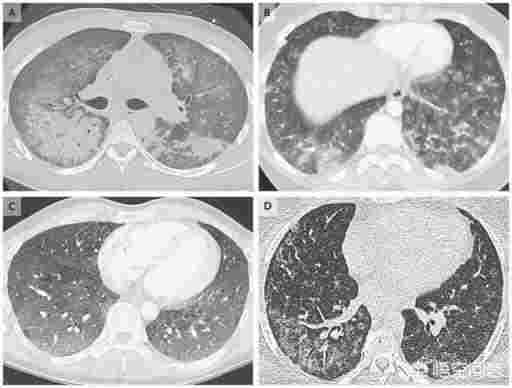

只能說這是一則非常抓人眼球的謠言。兩者最初被聯系起來是因為患者的X光片都可能出現白肺,也就是肺部浸潤性的炎癥。

但是白肺是多種肺炎共同的癥狀,并不能表明是什么引起了這個肺炎。電子煙肺炎和新冠肺炎不過從病因上還是癥狀上都存在許多區別。

目前對于電子煙肺炎的調查認為它的病因極可能是維他命E酸酯[1],一種不合法的電子煙增稠劑引起的化學性損傷, 而新冠肺炎是由新型冠狀病毒引起的病毒性肺炎[2]。